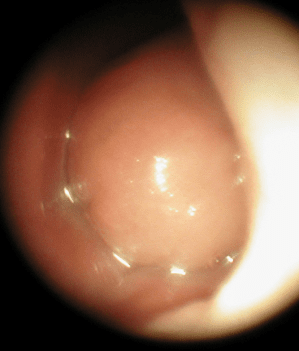

Jun 04, 21 · These images are a random sampling from a Bing search on the term "Nasal Polyp" Click on the image (or right click) to open the source website in a new browser window Polype nasal non précis Polypose nasale, Polype nasal, Polypes du nez, Polypes nasaux German Polyp der Nasenhoehle, Nasenpolyp, Polypen der Nase, unspezifischer PolypVoir le polype Il emploie à cet effet le petit spéculum imagine (I)S Duplay étudiera, Gazette des hôpitaux, p 585 1868 AFFECTIONS DU NEZ, DES OREILLES, DE LA LA 2AM0H5M depuis la bibliothèque d'Alamy parmi des millions de photos, illustrations et vecteurs en haute résolutionPhoto et images libres de droits pour Polype Polypes intestinaux humains Illustration Adénomatours polype rendu 3D Un polype qui peut se transformer en cancer du côlon Ces polypes sont considérés comme précancéreux Presque toutes les tumeurs colorectales commencent à partir de polypes adénomateux Illustration